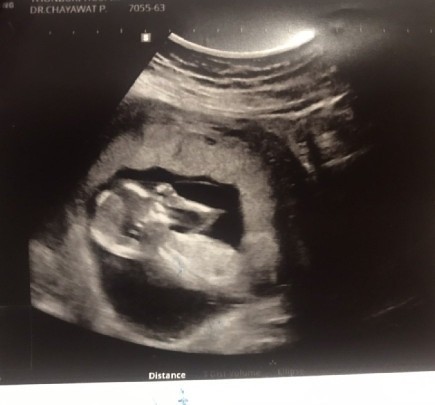

13 วีคค่ะ